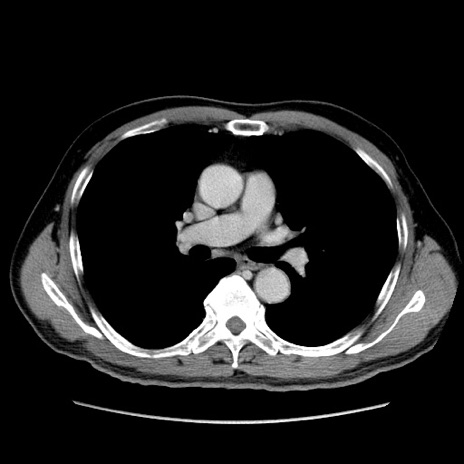

症例34(横断像)

【症例】60歳代 男性

【主訴】右鼠径部膨隆

【現病歴】1年程前より右鼠径部膨隆あり。自己にて還納可能だったため放置していた。3時間前より右鼠径部の脱出を認め、還納困難となり受診。

【既往歴】高血圧

【身体所見】右鼠径部に小児頭大の膨隆あり。弾性硬であり、用手還納は困難。左鼠径部にも膨隆を認める。脱出はなし。

【データ】WBC 15500、CRP 測定なし